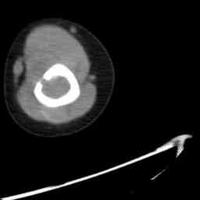

深度电极